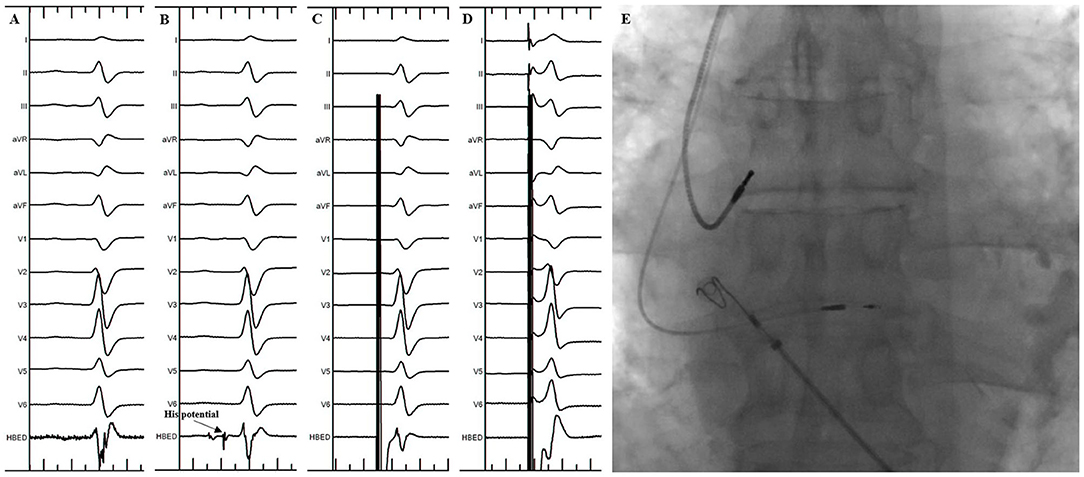

The procedure of HBP implantation in the standard group was the same as previously described (3). In brief, under the right anterior oblique 30° (RAO 30°) fluoroscopic view, the 3830 pacing lead was placed at the junction of the atrioventricular ring to search the ideal lead deployment site for HBP where the His potential could be recorded or the HB could be captured by unipolar pace mapping (Figure 1). The lead was fixed where the pacing parameters were satisfactory. The unsuccessful HBP were defined as: (1) the HB capture threshold or the correction threshold for bundle branch block (BBB) > 2.5 V/1 ms in three attempts; (2) the total FT was more than 20 min.

Figure 1. His Bundle Pacing implantation in the standard group. (A) Sinus rhythm before the procedure. (B) His potential was recorded during the procedure. (C) Selective His bundle pacing was confirmed at a lower pacing output. (D) Nonselective His bundle pacing was achieved at a higher pacing output. (E) Final lead location in the fluoroscopic image.